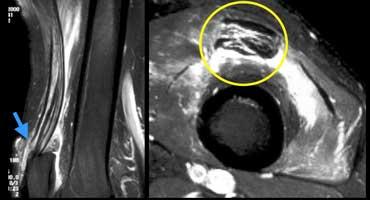

TRÁI: Các bó sợi ACL có hướng bình thường nhưng không bám vào lồi cầu đùi. PHẢI: Dấu hiệu hõm rỗng: dịch áp sát mặt trong lồi cầu ngoài.

Đôi khi dễ đánh giá hơn liệu các bó sợi có còn bám vào xương hay không khi quan sát trên mặt phẳng vành.

Tuyệt đối không được có dịch áp sát mặt trong lồi cầu ngoài.

Nếu có dịch ở vị trí này, được gọi là ‘dấu hiệu hõm rỗng’, cho thấy ACL đã bị bong khỏi điểm bám trên lồi cầu đùi.

Trên mặt phẳng ngang có dấu hiệu hõm rỗng (mũi tên vàng) ở vị trí lẽ ra ACL phải bám vào lồi cầu. Ở mức thấp hơn (sang phải), ACL đứt đã dính sẹo vào PCL (mũi tên xanh lá).

Trên mặt phẳng ngang cũng phải thấy dây chằng nằm sát bên lồi cầu.

Ở mức thấp hơn, chúng ta thấy ACL đứt bám dính vào dây chằng chéo sau.

Chúng đã dính vào nhau thành sẹo.

Đây là hình ảnh rất thường gặp trong đứt ACL mạn tính.

Sự dính sẹo này tạo ra góc gấp cấp tính của dây chằng.

Mặc dù ACL đã dính vào PCL, nhưng vẫn không đủ vững và cần phải tái tạo.